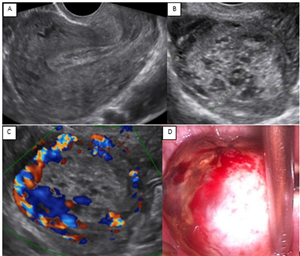

Thai ngoài tử cung ở buồng trứng